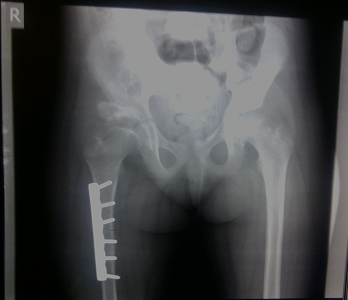

5.Рентгенограмма от 25.04.2015 правого предплечья в 2х проекциях+ после вправления в боковой проекции(в гипсовой повязке).

Заключение: определяется перелом костей правого предплечья в нижней трети со смешением отломков.

Заключение: После репозиции-стояние отломков удовлетворительное.

4)На основании лабораторных методов исследования 25.04.2015г рентгенограмма правого предплечья в 2х проекциях.

Выставлен следующий клинический диагноз: Закрытый перелом костей правого предплечья в нижней трети со смещением.